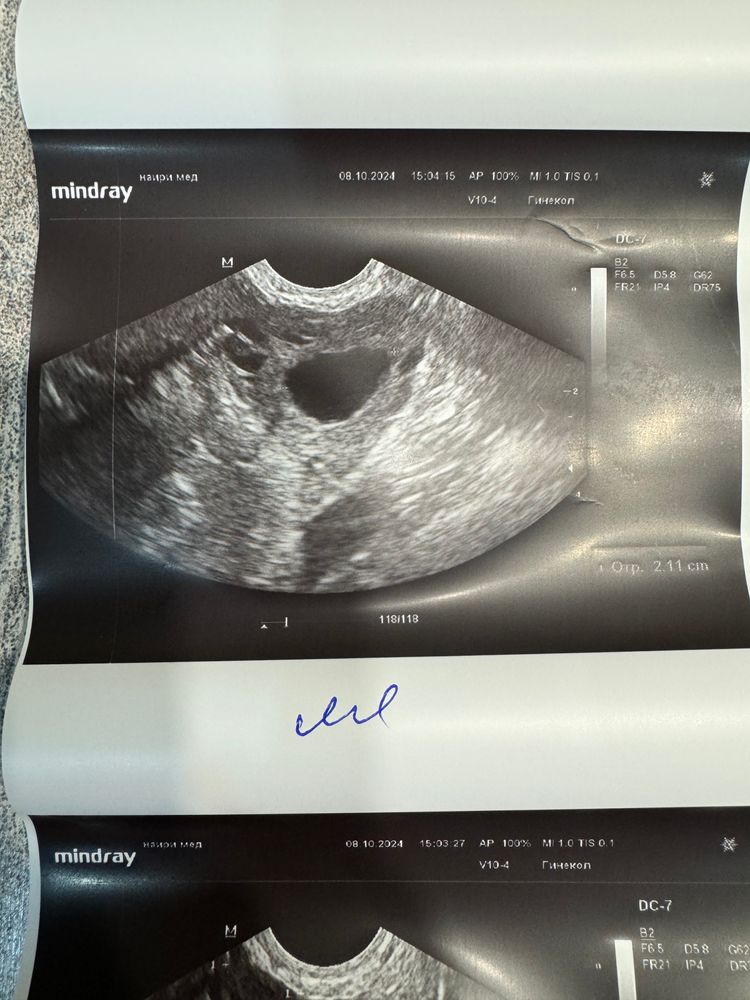

сходила платно на узи, сказали овуляция была в ближайшие два дня, желтое тело сформировано 19мм, эндометрий 12.7мм и хороший гормональный фон. В этот цикл конкретно хотела после двух ярких полос в день и на след день , а оказывается уже бы поздно было:)

Она сказала это 100% фолликул

Посчитала примерно сколько он вырос и сказала что он как раз на этих размерах лопает

Что вполне могли перепутать